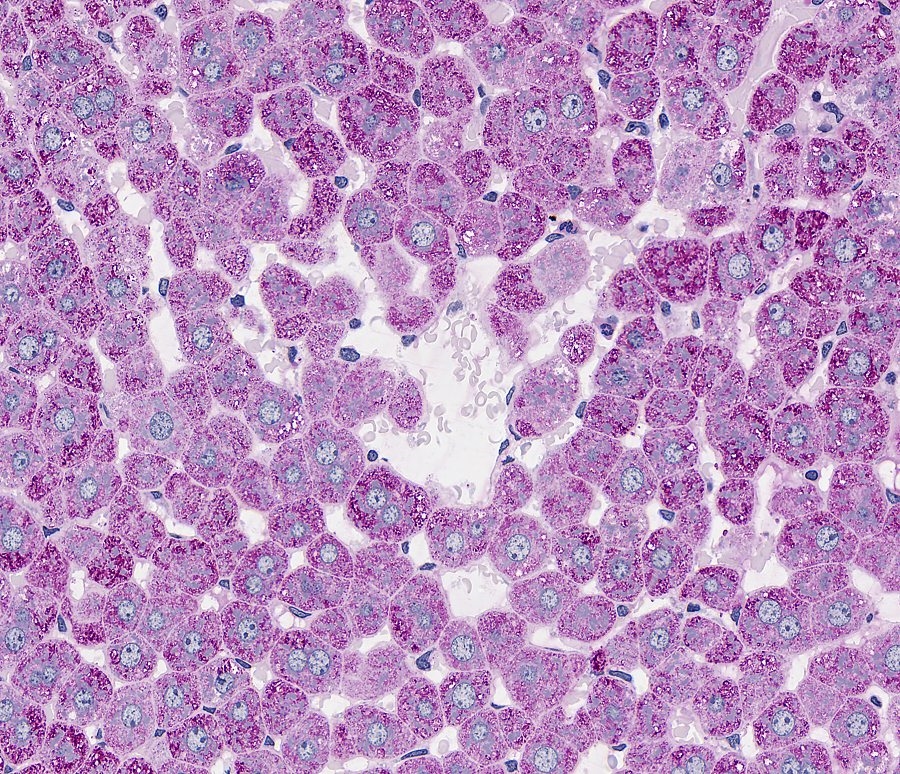

Bild 1 zeigt ein Leber Schnitt wo mit die PAS Reaktion Glykogen nachgewiesen wird.

Glykogen Färbt hier Purper/Rot.